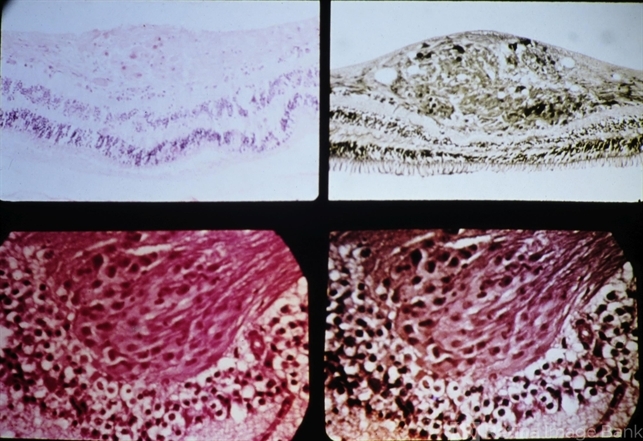

- diabetic retinopathy, cystoid, pseudonucleus

- Microinfarctions of the nerve fiber layer with cytoid bodies as seen in diabetic retinopathy (above) and hypertension (below). In each there are fusiform areas of swelling of the axons with the accumulation of material forming a pseudonucleus (cytoid body).